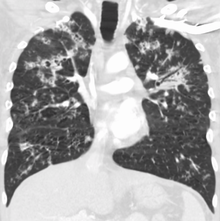

Miliary tuberculosis is a form of tuberculosis that is characterized by a wide dissemination into the human body and by the tiny size of the lesions (1–5 mm). Its name comes from a distinctive pattern seen on a chest radiograph of many tiny spots distributed throughout the lung fields with the appearance similar to millet seeds—thus the term "miliary" tuberculosis. Miliary TB may infect any number of organs, including the lungs, liver, and spleen.[2] Miliary tuberculosis is present in about 2% of all reported cases of tuberculosis and accounts for up to 20% of all extra-pulmonary tuberculosis cases.[3]

Testing for miliary tuberculosis is conducted in a similar manner as for other forms of tuberculosis, although a number of tests must be conducted on a patient to confirm diagnosis.[5] Tests include chest x-ray, sputum culture, bronchoscopy, open lung biopsy, head CT/MRI, blood cultures, fundoscopy, and electrocardiography.[11] The tuberculosis (TB) blood test, also called an Interferon Gamma Release Assay or IGRA, is a way to diagnose latent TB. A variety of neurological complications have been noted in miliary tuberculosis patients—tuberculous meningitis and cerebral tuberculomas being the most frequent. However, a majority of patients improve following antituberculous treatment. Rarely lymphangitic spread of lung cancer could mimic miliary pattern of tuberculosis on regular chest X-ray. [16]